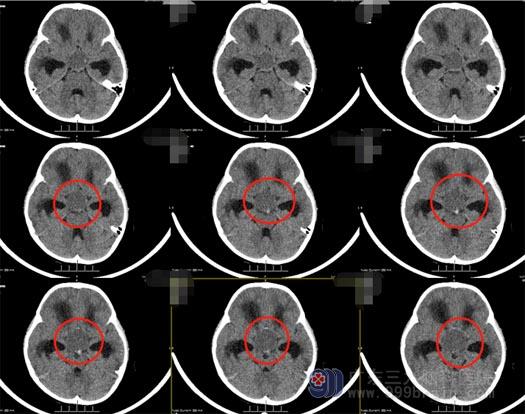

于是,他们联系了之前的主管医生——神经外五科副主任卢建侃,卢建侃看过小妍的头颅MR检查报告后认为:孩子脑积水严重,应尽快手术治疗。小妍父母一点不敢耽搁,赶紧带着孩子来到广东三九脑科医院。我院头颅CT提示:鞍上占位性病变、脑积水。这是的小婷已经是嗜睡状了。

鲁明副院长和神经外五科王国良主任带领治疗团队进行了详细的病例讨论:患儿嗜睡状,哭声间断,呕吐,头颅CT提示鞍内、鞍上、三脑室巨大占位:颅咽管瘤?梗阻性脑积水。患者脑积水严重,家属同意后急诊给予脑室外引流;次日行鞍内、鞍上、三脑室巨大占位切除术,术中见肿瘤起源于垂体柄中央,瘤内减压后沿着肿瘤的包膜切除肿瘤,患者双侧下丘脑被肿瘤侵犯,予肿瘤全切,手术过程顺利。